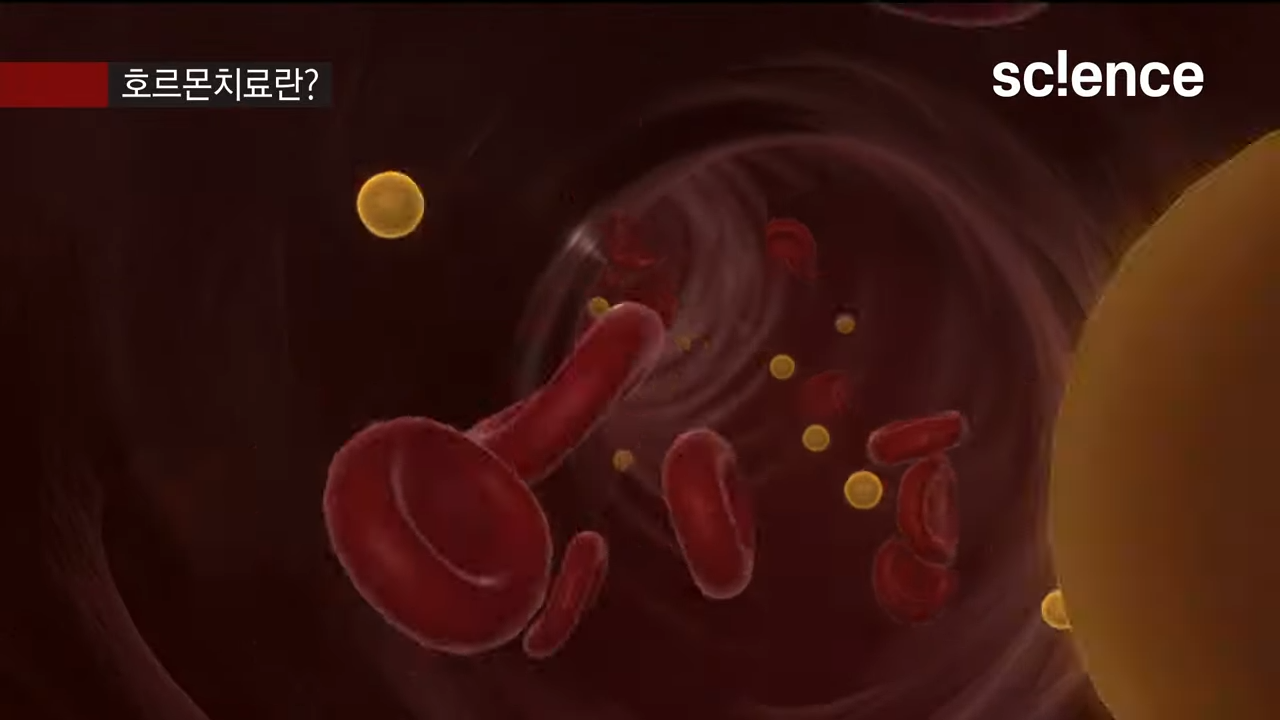

EBS 컬렉션 사이어스 - 유튜브 영상

명의가 알려주는 전립선암